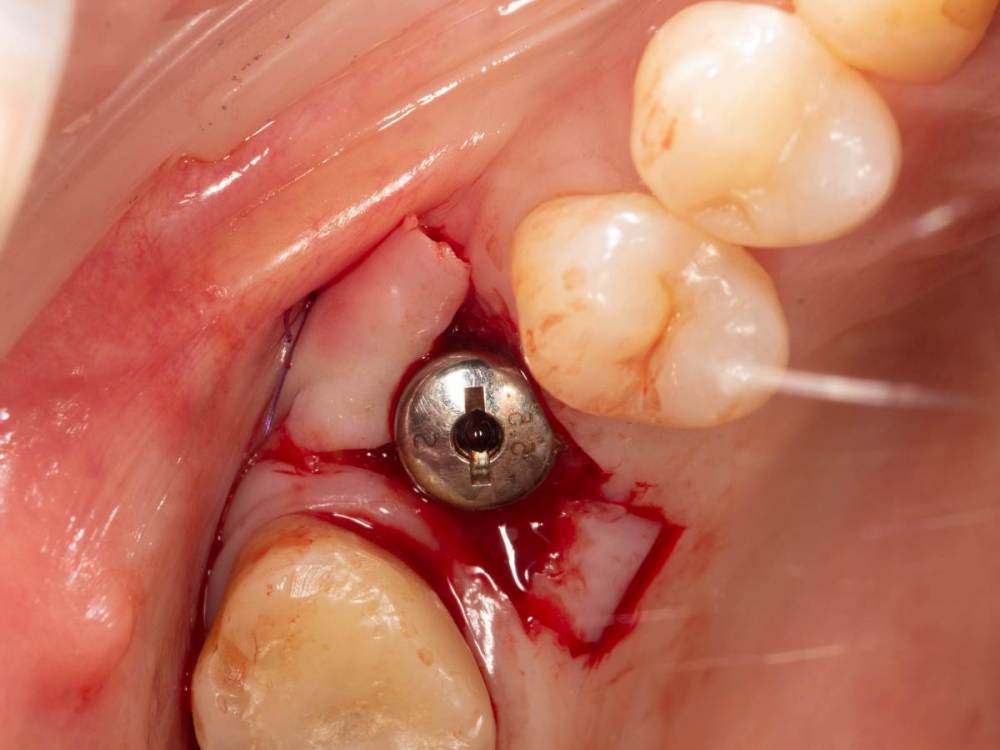

Женька Опубликовано 3 октября, 2022 Поделиться Опубликовано 3 октября, 2022 Открывал я снова тут имплантат roll техникой. И взбрело в голову, мол нёбно то много отрезал. Решил попробовать сделать скользящий нёбный лоскут. Как вы уже наверное догадались, ничего из этого не вышло . Лоскуток нёбный поначалу вроде даже смещался скользя, но далее превратился в СДТ маленький, который пришлось с определёнными трудностями возвращать хотя бы обратно на место (хорошо хоть не засосало в слюноотсос). Собственно вопрос, где и как можно данной методике научиться? может почитать где-то можно. У первоисточника хотелось бы, конечно) но трудно осуществимо. 1 Ссылка на комментарий